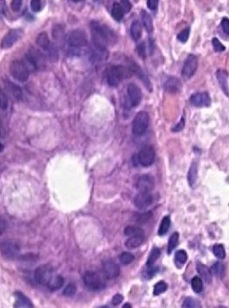

However, nuclei and glands instance segmentation cannot be regarded as a simple task for non experts in pathology labs. Despite being continuous advancements in learning algorithm, nuclei segmentation is still an extremely challenging task because of blurred nuclei boundaries, differences in size and shape highlighted by Vahadane et al. [12], uneven staining, pathological changes on pathological images, morphological abnormalities [13] and substantial color variations described by Rashmi et al. [14]. Similarly, varying morphology of glands at different histological grades, different intrinsic features of glands WSIs poses major challenge during segmentation of instances. Firstly, applying mathematical shape model for instance segmentation gets difficult due to shapes heterogeneity. Figure 2 shows structural variations of nuclei in different organs. Secondly granule filled cytoplasm cause nucleus extrusion to flat shapes as compared to oval or round structures in normal cases mentioned by Yan et al. [15]. Thirdly, cellular matrix variations results in anisochromasia thus resulting in additive noise in background compared to normal intensity gradients.

Improper staining often times result in similarity in nuclei to cytoplasm or background colors thus yielding blurred boundaries [16]. Moreover occurrence of several overlapping nuclei in whole slide images causes further difficulty in objects segmentation. Major challenge in model development is varying types of nuclei e.g nerve cell nuclei are typically triangular in shape [17], while glial and oligodendrocytes nucleus are usually round in appearance but the later one have light rings as, astrocytes have oval shape, endothelial cells are usually slender in structure [18], while malignant tumor cells have irregularly shaped nuclei [19]. Developed model is supposed to be robust enough to detect all these kinds of nuclei without any mislabelling. Digital image quality variation, background clutter, image artifacts are some other extremely important yet least discussed problem in this domain. Nuclei curvature variation also impacts detection since normally in pathology images, nuclei contour points curvature changes smoothly [20]. However, given a single contour having two or more touching or occluding nuclei, results large curvature change at touching points. Already existing automated medical image analysis tool use classical segmentation including active contour models, watershed or thresholding techniques for nuclei instances identification. These tools needs configuration with respect to each data to accurately analyze distinct microscopic modalities including scales and experimental variation, thus leading to an evident requirement of technological domain expertise for accurate algorithm selection and parameters adjustment. Still for proficient ones too, this choice can be daunting, considering that every year numerous papers are published, presenting new research techniques for gland and nucleus instance segmentation. Even after examining under controlled experimental conditions, no single technique can be generalized for segmenting all microscopy images correctly, since classical machine learning algorithms are either sensitive to technical artefacts or often fails in adapting to biological samples heterogeneity. Altogether, this situation yields slows pace of research and at times inhibits research laboratories from adopting newer image analysis technologies owing to the time and expertise required.